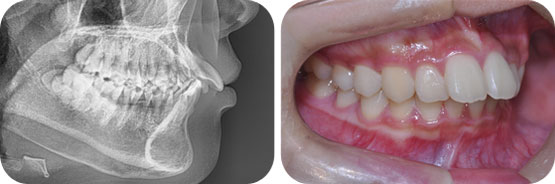

덧니교정( 청소년 교정:비 발치 교정 /악궁 확장장치+미니스크류+약간의 치간삭제 교정)

Before

After